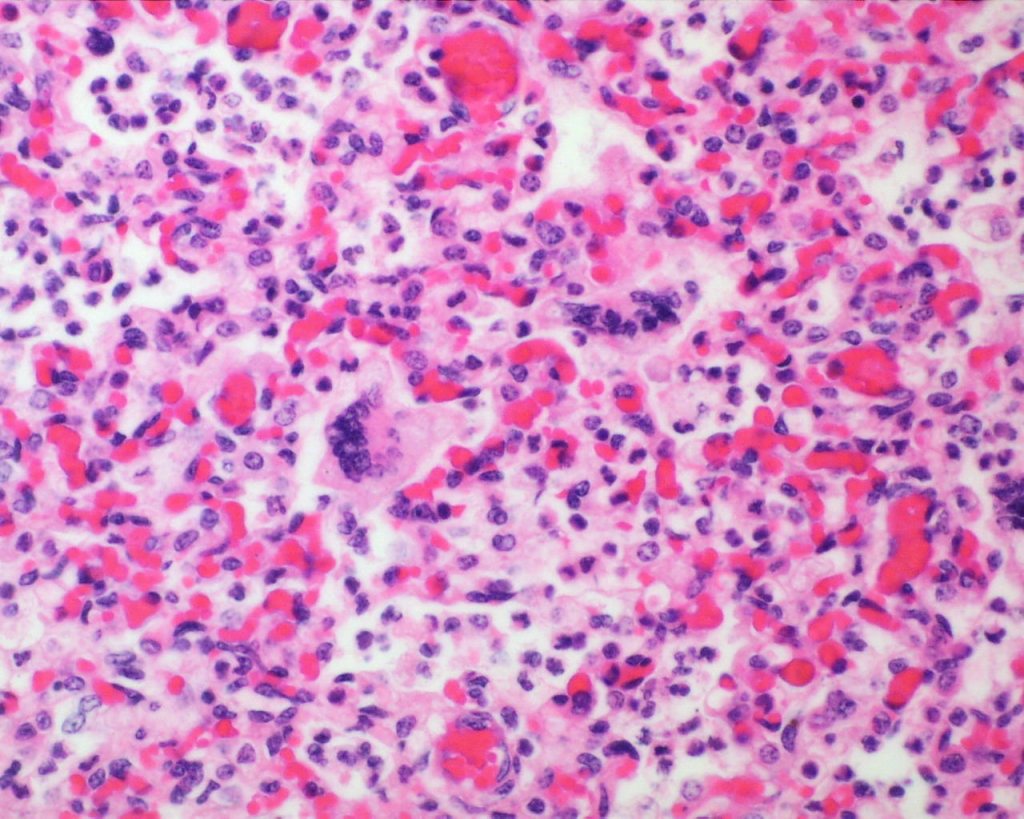

Focal hemorrhages may also be found in the airways usually with evidence of hemorrhages in other organs suggestive of disseminated intravascular coagulation and shock (Fig 21).

The mechanism for many hemorrhages is obscure. With elevated left atrial pressure, for example with heart failure, but more acutely with closure of the ductus arteriosus, elevated atrial pressure would be reflected in dilatation of the pulmonary veins in the septa (Fig 22).

In turn this pressure should passively increase pulmonary capillary pressure. A similar increase in atrial pressure occurs with sudden acute twin transfusion prior to death (Fig 23).